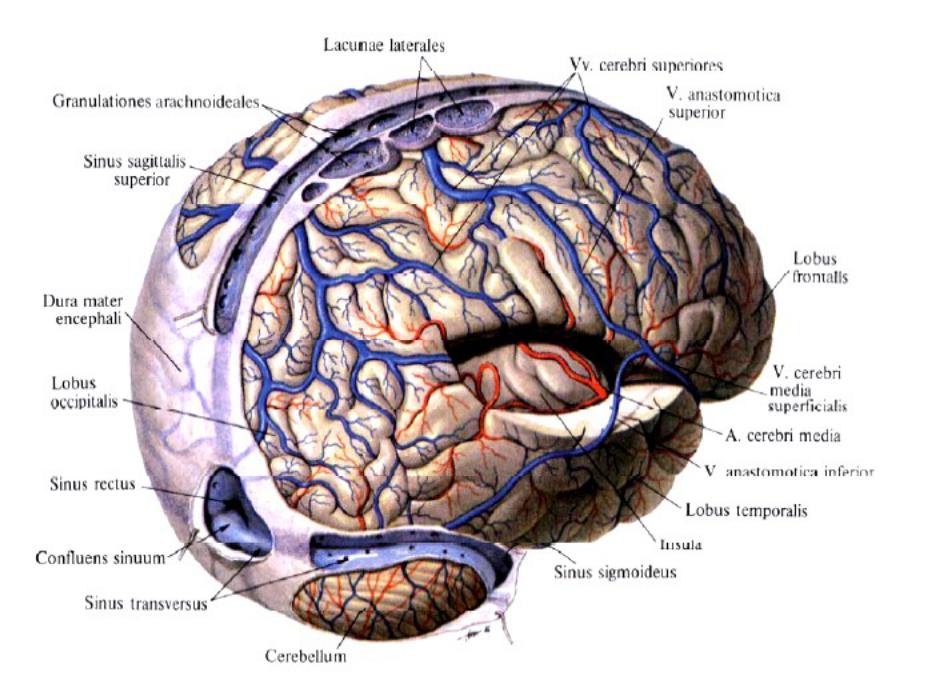

Анатомия внутренней яремной вены: КТ изображения